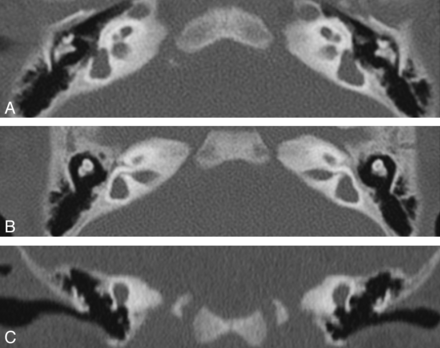

Patient J. CT. Axial views (A and B) through the cochlea and the vestibule show the flattened apex and midturn of the cochlea. The vestibular cavity is large and shows evaginations that could represent SCC anlages. The vestibular aqueduct is visible and is not dilated. Coronal view (C) favors the hypothesis of a lateral SCC anlagen. The superior SCCs are absent, but the superior margin of the vestibule is convex and a small anlagen cannot be excluded.

Patient M. CT. Axial views (A and B) through the cochlea and the vestibule show a small cochlea, flattened with a partition hardly visible and atresia of cochlear nerve canals, an enlarged vestibular cavity, and agenesis of all of the semicircular canals. Coronal view (C) confirms the absence of the superior and lateral SCC. Posterior deformity of the vestibule cannot exclude an anlage.